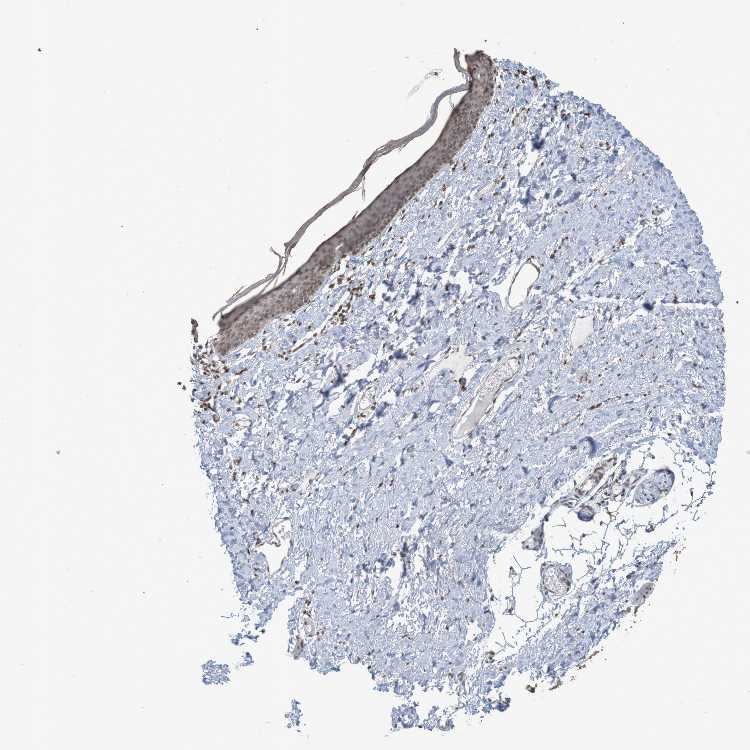

SKIN 2 - Antibody stainingi

Antibody staining in the annotated cell types in the current human tissue is reported as not detected, low, medium, or high, based on conventional immunohistochemistry profiling in selected tissues. This score is based on the combination of the staining intensity and fraction of stained cells.

Each image is clickable and will lead to virtual microscopy that enables deeper exploration of all samples and also displays staining intensity scores, fraction scores and subcellular localization as well as patient and tissue information for each sample.

Antibody CAB011197

Epidermal cells Medium